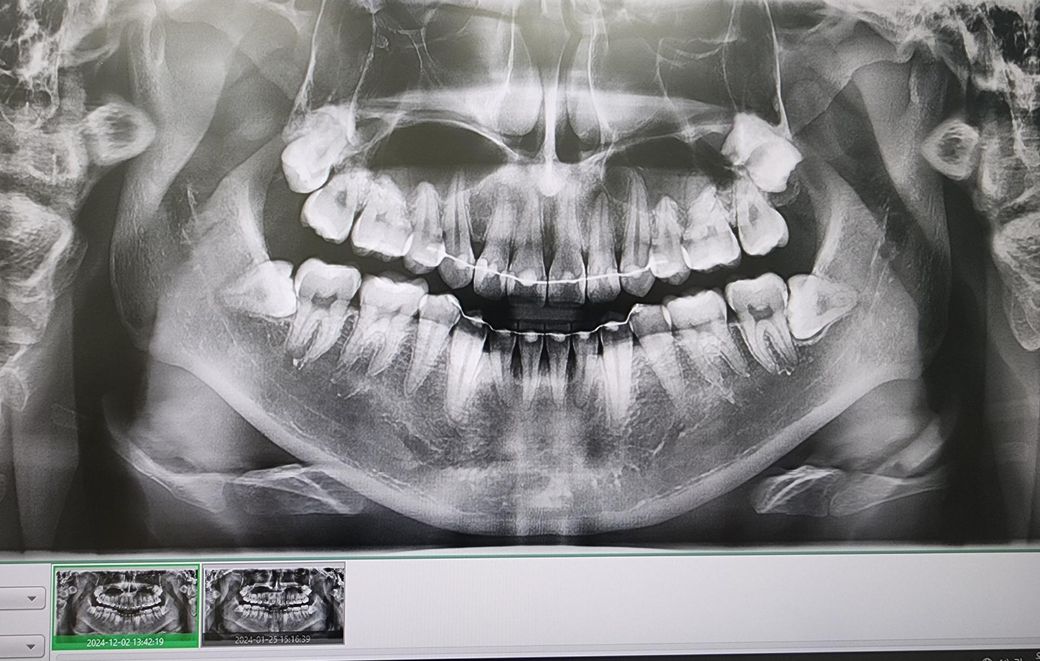

치과의사분들 파노라마 사진 봐주세요

25 06월입니다 혹시 문제점있나 봐주실수있으실까요

치료해야되는부분이나 미리감사합니다

아프거나 시린곳은 없습니다

• 1번 째 사진

파노라마 상으로는 어금니 치아 사이에 충치가 잇는것처럼 보이는곳도 잇으니 치과에가셔서 작은사진을 몇장 찍어보시는게 좋을것같습니다.

잇몸뼈 높이 변화 크게 없고요 특별히 치료가 시급한 큰 충치도 보이진 않습니다 다만 오른쪽 아래 사랑니는 발치 고려해봐야 할 것 같습니다